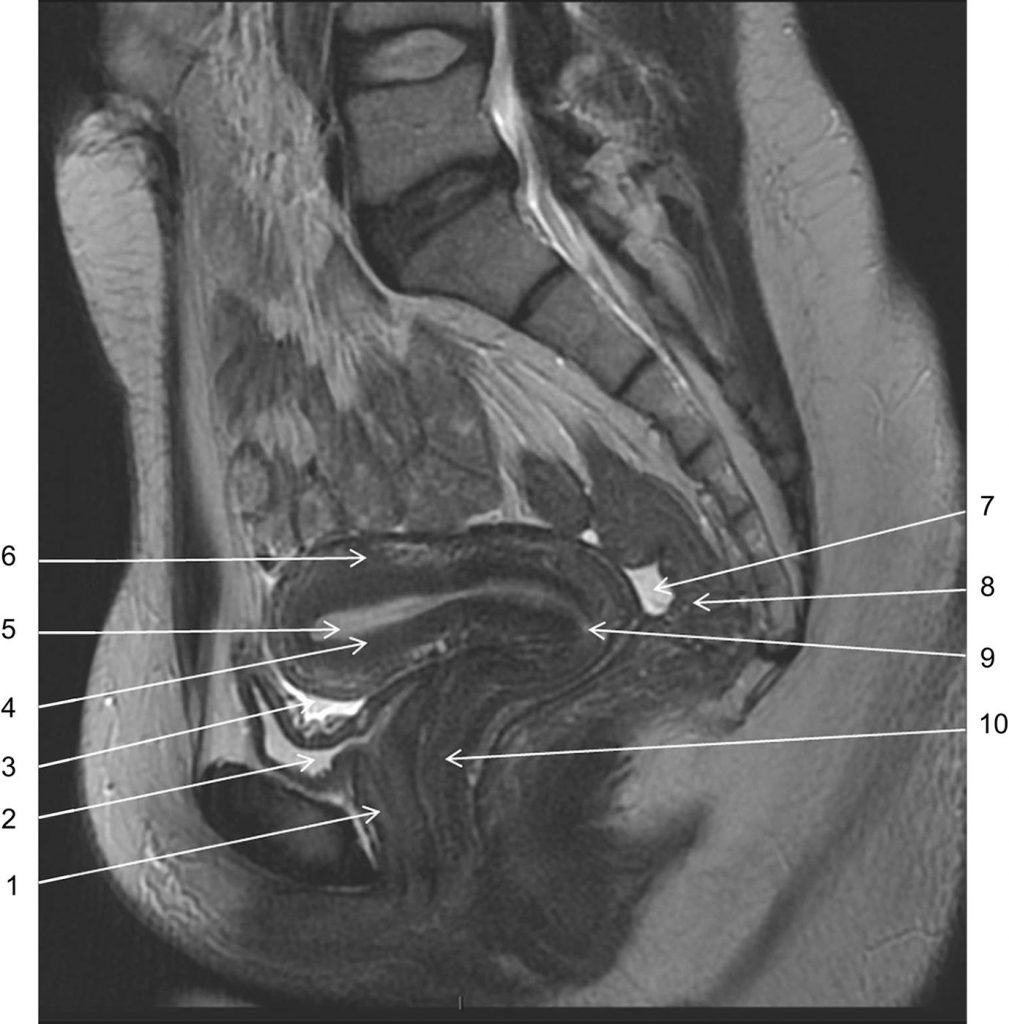

Fig. 19.2. Coupe IRM dans le plan sagittal en pondération T2 passant par la ligne médiane.

1. Urètre. 2. Vessie. 3. Cul-de-sac vésico-utérin. 4. Zone jonctionnelle. 5. Endomètre. 6. Myomètre. 7. Cul-de-sac recto-utérin (de Douglas). 8. Rectum. 9. Col utérin. 10. Vagin.

Source : CERF, CNEBMN, 2022.